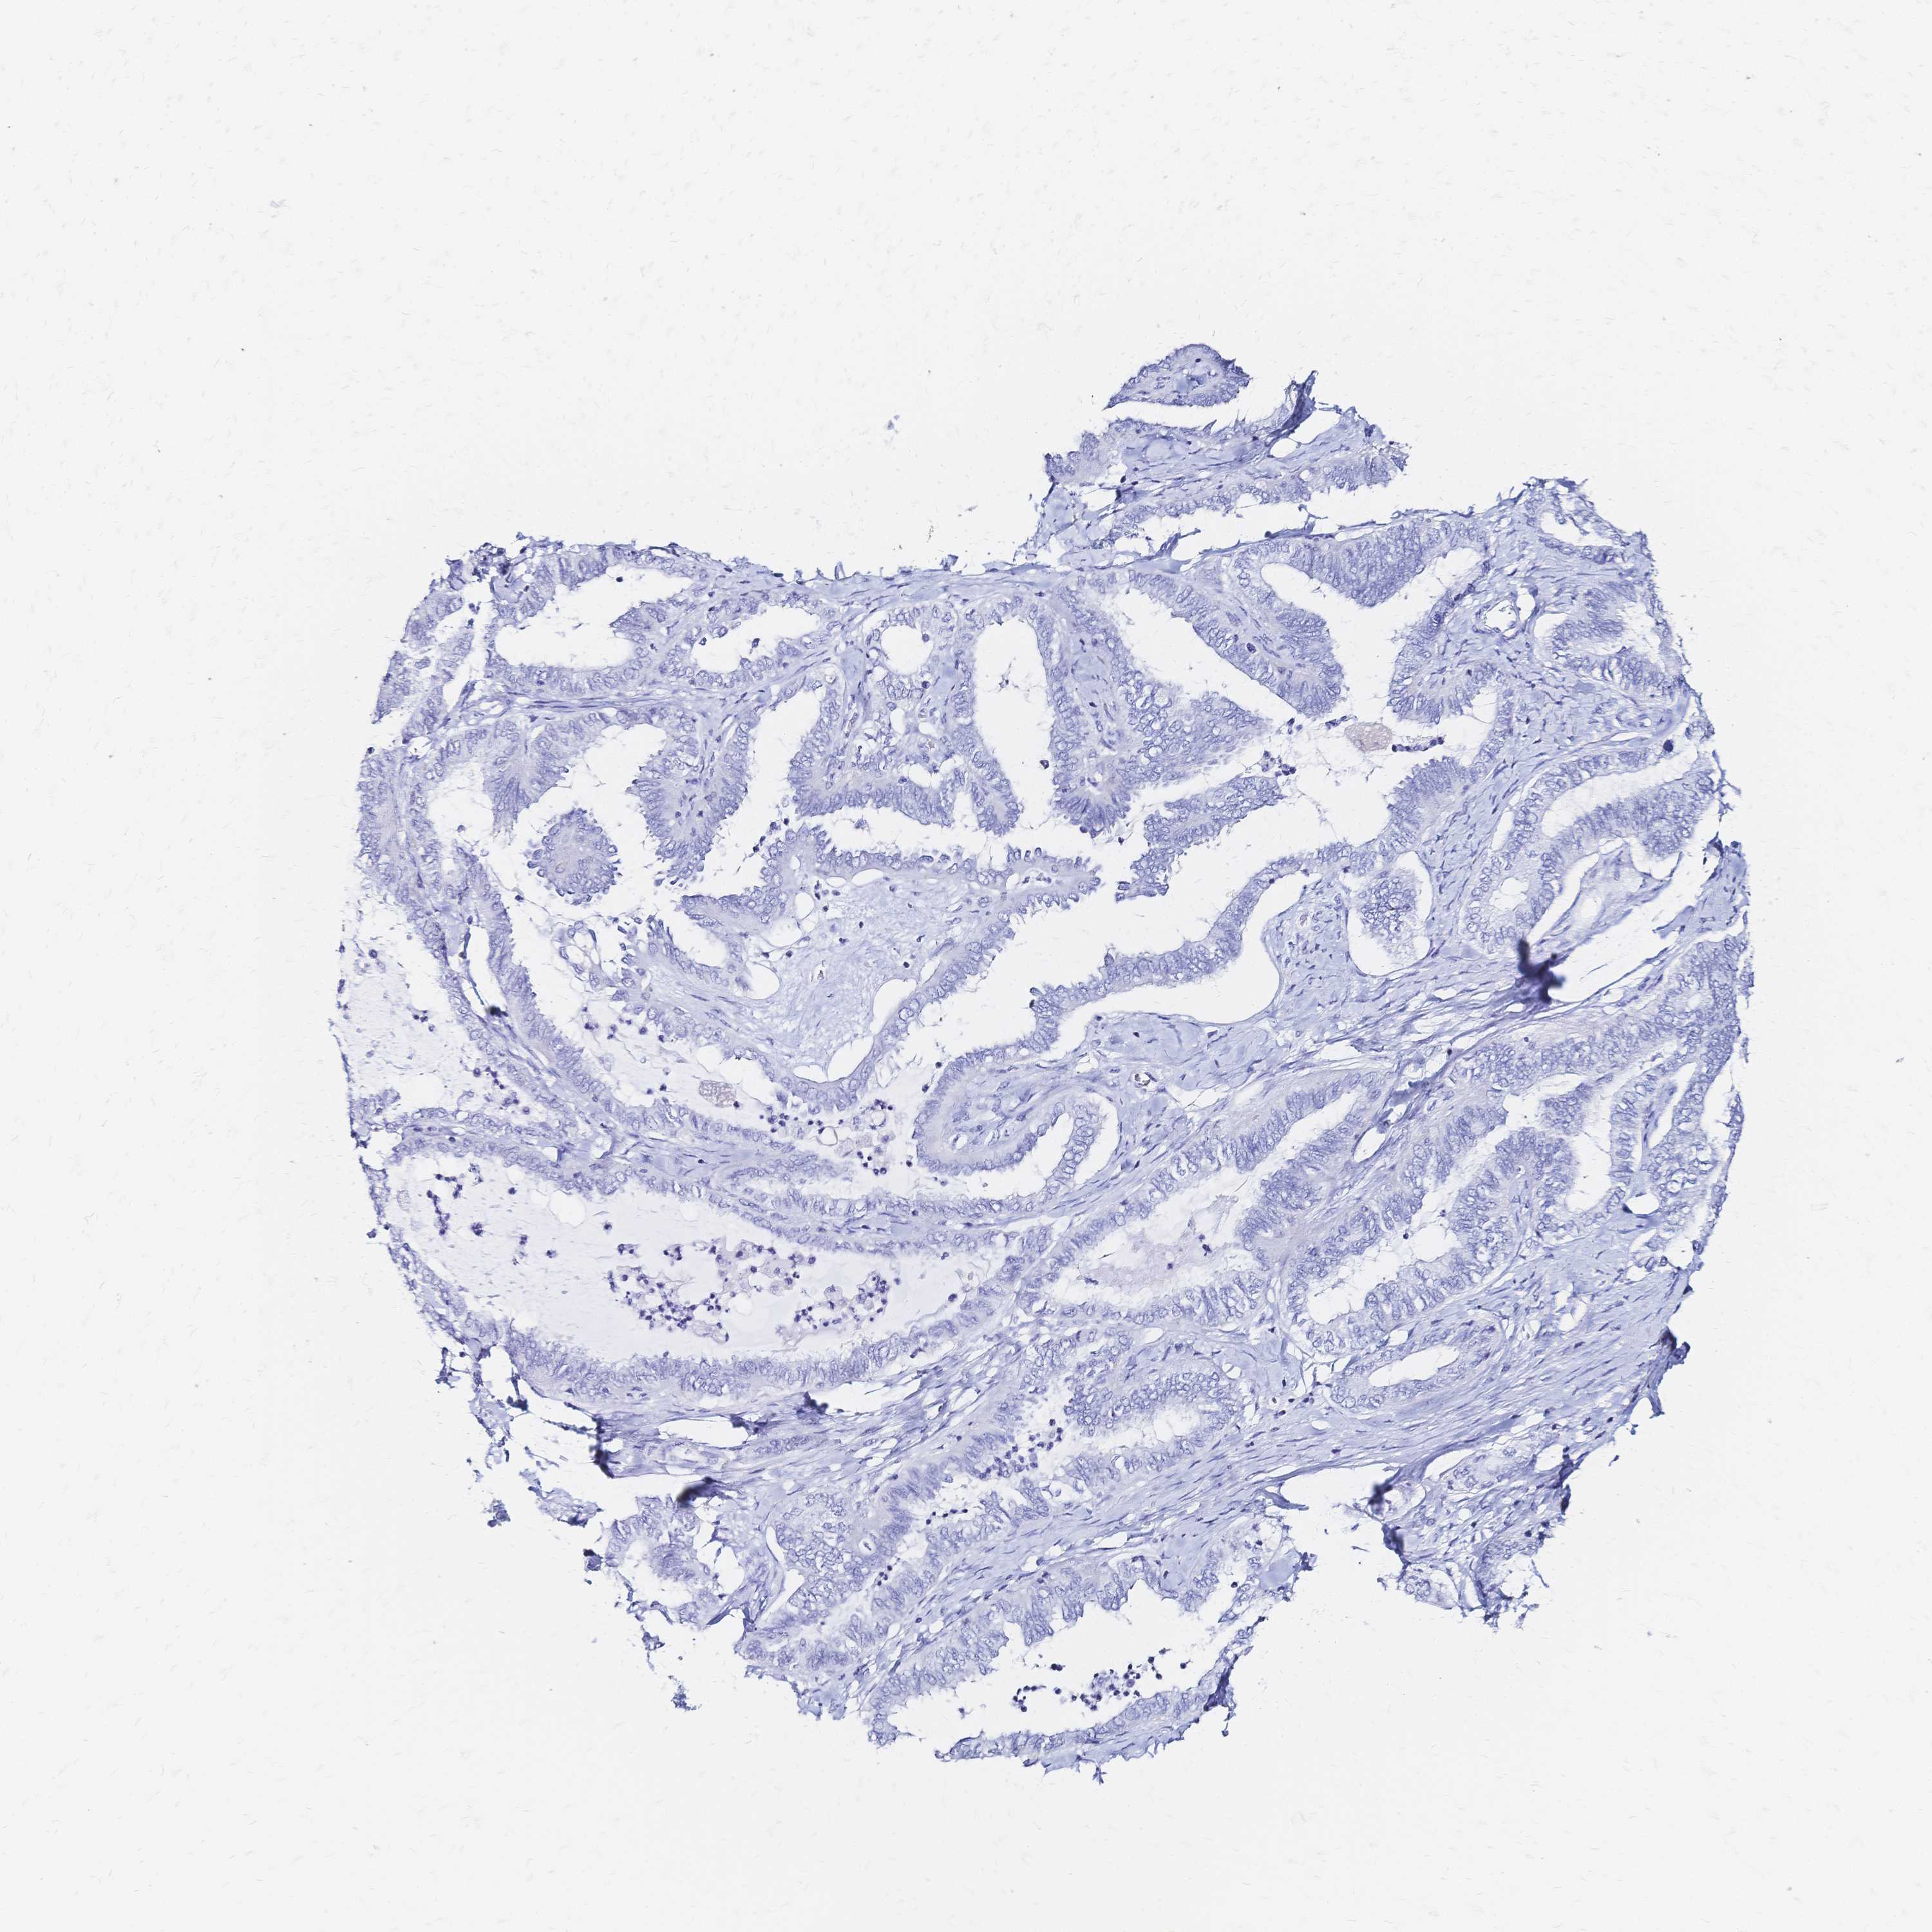

OVARIAN CANCER - Protein expressioni

A mouse-over function shows sample information and annotation data. Click on an image to view it in a full screen mode. Samples can be filtered based on level of antibody staining by selecting one or several of the following categories: high, medium, low and not detected. The assay and annotation is described here.

Note that samples used for immunohistochemistry by the Human Protein Atlas do not correspond to samples in the TCGA dataset.

Antibody stainingi

Antibody staining in the annotated cell types in the current human tissue is reported as not detected, low, medium, or high, based on conventional immunohistochemistry profiling in selected tissues. This score is based on the combination of the staining intensity and fraction of stained cells.

Each image is clickable and will lead to virtual microscopy that enables deeper exploration of all samples and also displays staining intensity scores, fraction scores and subcellular localization as well as patient and tissue information for each sample.

Antibody HPA051805

Antibody HPA055106

Antibody CAB015467

Staining

High

Medium

Low

Not detected

Intensity

Strong

Moderate

Weak

Negative

Quantity

>75%

75%-25%

<25%

None

Location

Nuclear

Cytoplasmic/membranous

Cytoplasmic/membranous,nuclear

Cystadenocarcinoma, serous, NOS

Cystadenocarcinoma, mucinous, NOS

Carcinoma, endometroid